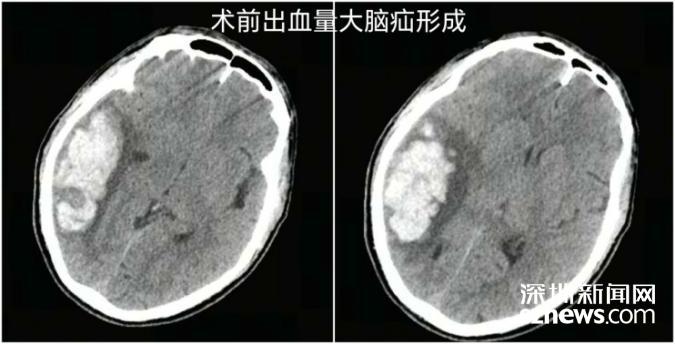

据南科大医院神经外科鲁春鹤主任介绍,患者当时右侧顶枕颞叶脑出血量高达约40mL,右侧大脑半球脑水肿、大脑镰下疝接踵而至,生命体征急速恶化,大脑里破裂的血管如同随时可能引爆的“定时炸弹”,情况岌岌可危。